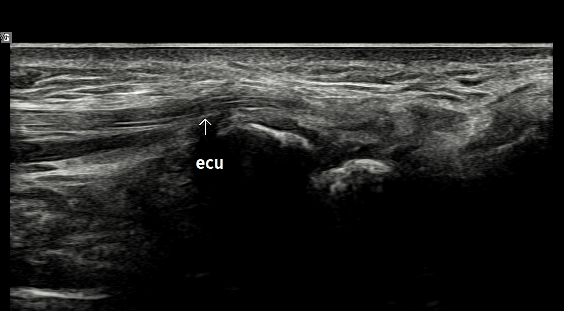

- 치료기간 : 25 .6 .19 ~ 25 . 10 . 23

- 치료횟수 : 15 회 (아피톡신+극초단파)

치료 전 (족저근막 두께 0.44~0.61cm)

치료 후 (족저근막 두께 0.33~0.36cm)